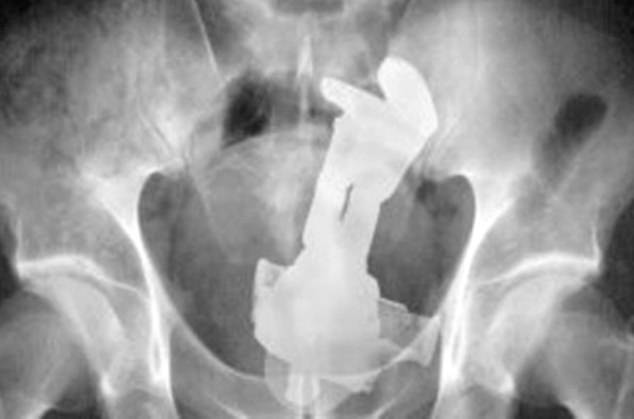

2. Έναν πρωταγωνιστή από το Toy Story, τον Buzz Lightyear